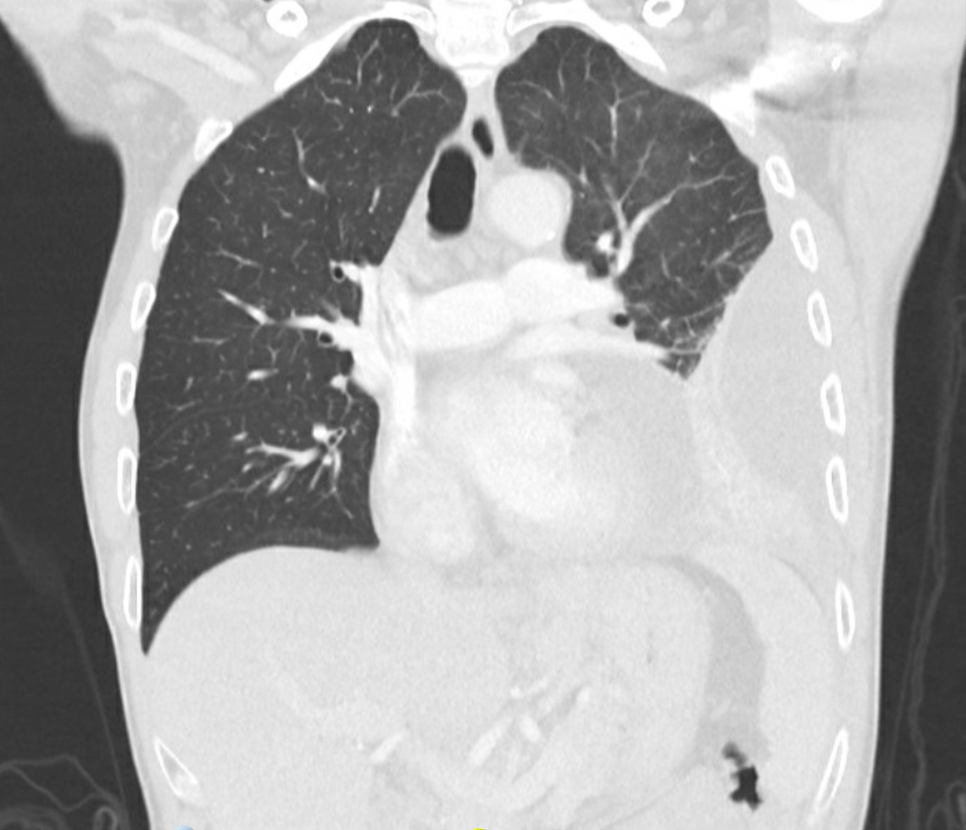

CP9 CT: CT confirms consolidation surrounded by effusion with multiple loculations (not easily seen above), consistent with your diagnosis.

Teaching points. In patients with cardiopulmonary complaints, POCUS can rapidly narrow/inform your differential and guide further tests and treatment. In this case, remember to consider empyema in patients with recurrent pneumonia, not responding to antibiotics, or with suspicion of parapneumonic effusion (a pleural fluid collection secondary to pneumonia; if this contains pus, it is considered an empyema, and these can develop fibrous loculations). With recent changes to IDSA guidelines for pneumonia treatment, anaerobic coverage is now only required for empyemas (aspiration pneumonia alone no longer qualifies). Empyemas also often require operative drainage for successful source control, which may involve fibrinolysis to break up loculations.